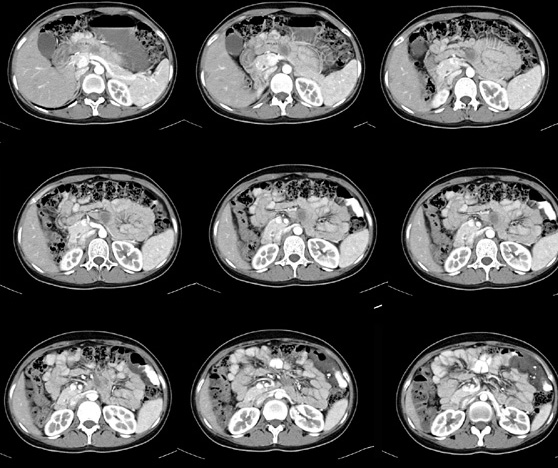

女性,28岁,停经3月,腹部膨隆1月,产前检查发现腹部占位

{肿块中心ct值27hu,增强后,动脉期、门脉期均无明显强化)

1 肠系膜肿块诸期无明显强化,肠系膜血管包绕其中但其周围仍见脂肪称“脂肪环征”;2 肠系膜血管远端较近端细,于重组像上见血管周围有强化结节为炎性结节,3肿块内见部分脂肪密度及少许点状钙化。4 腹膜后无肿大ln。

需与恶性病变鉴别,脂肪环征为重要点。亦需与卵巢源性肿瘤鉴别,年龄以及未见“卵巢静脉征”为要点。

患者手术病理:腹腔囊性淋巴管瘤,象这样充满整个腹腔的的确很少见